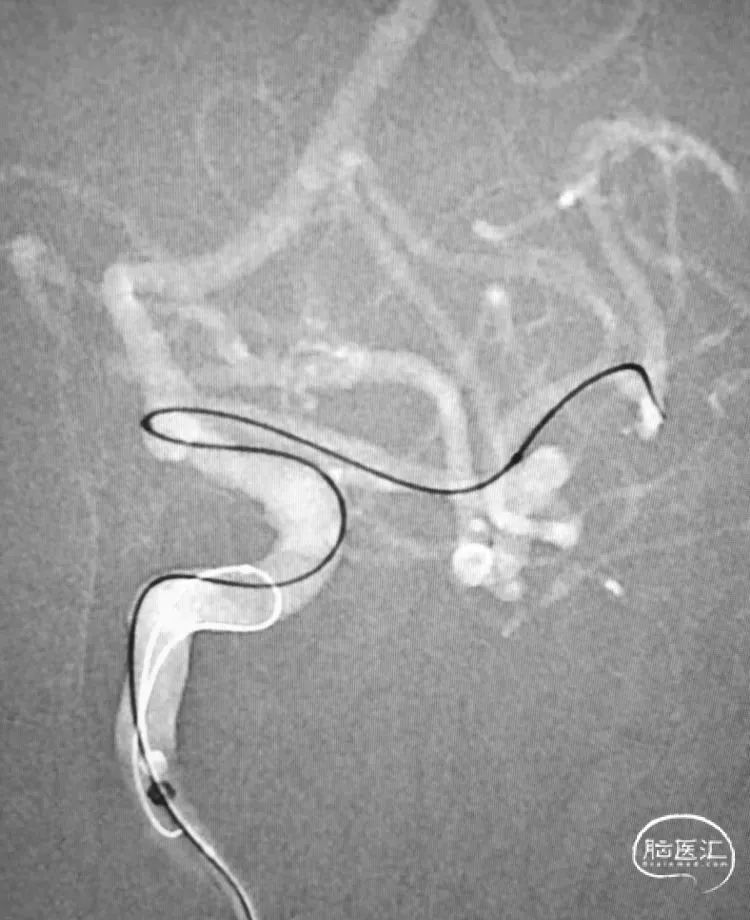

通路解决就简单多了,SL-10到位。

直接释放Atlas3.0支架。

同一根导管,稍微回退一点,直接穿网眼,超乎想象的顺利!

后面的操作就没有悬念了。

手术顺利完成,鸣金收兵!